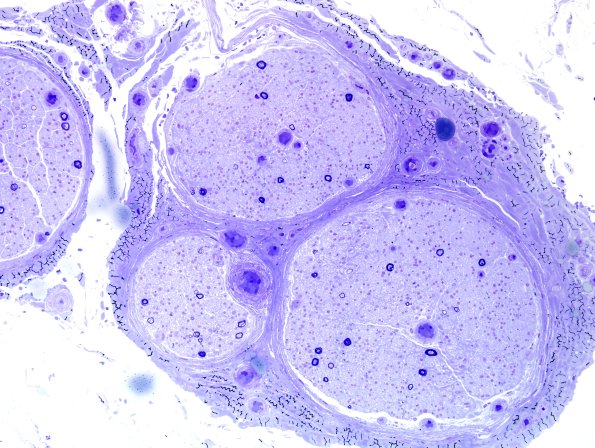

Washington University Experience | PERIPHERAL NEUROPATHY | 4 AXONAL DEGENERATION | 2 Plastic Sections | 23A1 End-stage nerve (Case 23) Plastic 6.jpg

The patient is a 54-year-old male with a history of monoclonal paraproteinemia with amyloidosis. Operative procedure: Left sural nerve biopsy. ---- 23A1,2 One micron plastic sections demonstrate marked loss of large and small myelinated axons. The remaining axons are predominantly large myelinated forms. They are accompanied by axons which have myelin sheaths which are too thin for axon caliber, evidence of axonal degeneration and regeneration, although regenerated clusters are very rare.